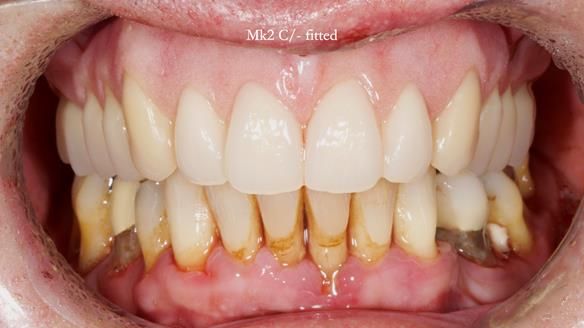

We sacrificed the upper canine roots and made a Mk2 temporary complete denture to provide more tongue space and improve speech.

Twelve months after the final extractions, I made the Mk3 definitive complete upper denture.

- Retention, stability and support were excellent.

- Speech was good but not perfect.

- Aesthetics were excellent and Jeremy was very happy with this apspect.

- Sibilance with S’s was still a bit of a problem for him, however, Claire (my nurse) and I could not hear problems with the speech.

- Biting and chewing were no problem at all.

- Amazing improvement in oral hygiene and response to Syed’s periodontal therapy.